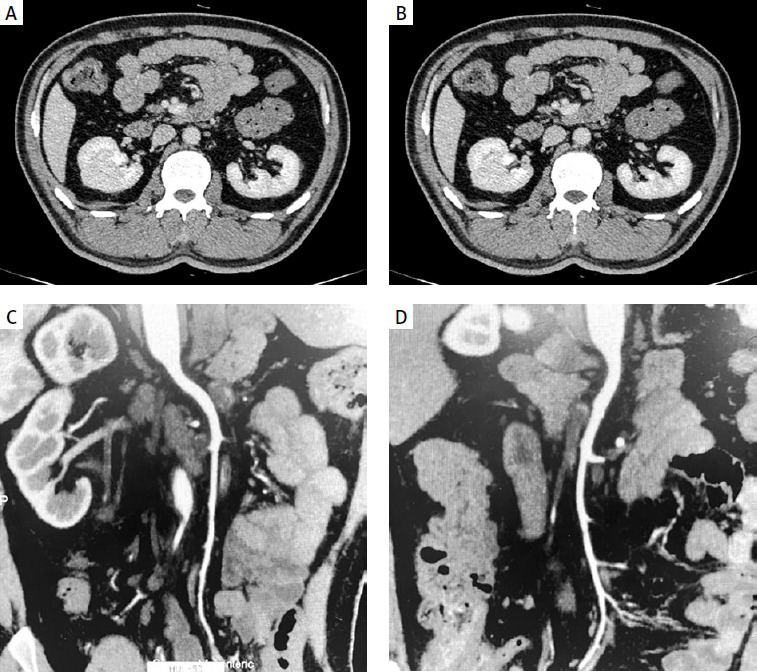

A 45-year-old male patient was referred to our hospital with a 1-day history of melena, dizziness, palpitations, weakness, and transient loss of consciousness. On examination, he appeared pale. Laboratory tests were all within the normal range except for iron deficiency anemia (Table I). Chest and abdominal computed tomography (CT) were unremarkable. Gastroscopy revealed no bleeding site. An ultrasound scan of the abdomen showed normal appearance of the liver, spleen, and pancreas. No signs of thrombosis of the portal axis were detected in Doppler examination. Colonoscopy revealed exaggerated vasculature of the colon (varices) (Figure 1). Mesenteric CTA indicated tortuous and increased varicose veins in the transverse colon, ascending colon and small intestine (Figure 2). The case was discussed, and a decision was made to proceed with internal medicine conservative treatment with fasting, nutritional support, and fluid therapy. The patient made an uneventful recovery and was discharged. The patient had hemorrhage of the digestive tract again 1 year later. The evidence again demonstrated total colonic varices, and the patient was advised surgery but declined the procedure.

The diagnosis and etiology of idiopathic colonic varices are difficult to determine, and require laboratory and imaging tests to rule out secondary causes. Relevant tests to be completed include: blood routine, liver function, hepatitis serology, liver ultrasound, portal vein ultrasound, portal venography, and liver elastography. CT angiography or mesenteric angiography is the most accurate diagnostic tool [7]. Angiography shows dilated vessels and prolongation of the venous phase. Colonoscopy is a diagnostic option. During the endoscopy, colonic varices are identified by dilated, tortuous vascular tracts with a bluish tinge on the mucosal surface. Our patient was diagnosed appropriately with colonic varices through CT angiography and colonoscopy.